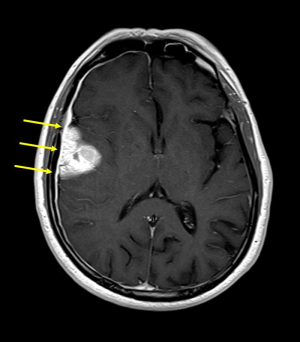

Die Klassifikation der Weltgesundheitsorganisation (WHO) beinhaltet mehr als 130 verschie-dene Tumorarten, die das Gehirn, das Rückenmark oder das periphere Nervensystem be-treffen können. Zu den häufigsten Tumoren gehören die Gliome, die im Gehirn selbst wach-sen (Abbildung 1), Meningeome, die von den Hirnhäuten ausgehen und von aussen das Ge-hirn komprimieren (Abbildung 2), Metastasen («Absiedlungen»), die von ausserhalb des Nervensystems wachsenden Tumoren über die Blutbahn in das Gehirn streuen, und Tumo-ren der Hirnanhangsdrüse (Hypophysentumoren). Je nach Verhalten unterscheidet die WHO vier Tumorgrade, wobei Grad I häufig durch ein langsames (z.B. Meningeom), Grad IV durch sehr aktives Wachstum charakterisiert ist (z.B. Glioblastom).

Die von Hirntumoren verursachten Symptome sind charakteristisch für die Gehirnregion, in der ein Tumor wächst. Frühe Anzeichen können allerdings so unspezifisch sein, dass sie nicht mit einer Tumorkrankheit in Verbindung gebracht werden. Kopfschmerzen kommen in ca. 30% vor. Häufig treten epileptische Anfälle, Lähmungserscheinungen und Sprach- oder Sehstörungen auf. Bei Verdacht auf das Vorliegen eines Tumors wird als wichtigster diag-nostischer Schritt eine Magnetresonanztomographie erforderlich (MRI, Schnittbilduntersu-chung, Abbildungen 1–2). Zur Klassifikation des Tumors muss das Tumorgewebe mikrosko-pisch untersucht werden. Hierzu wird eine Operation erforderlich. Zur Vorbereitung eines möglichst schonenden Eingriffs können wichtige Funktionsareale des Gehirns mittels funktio-neller Magnetresonanztomographie (fMRI) und Darstellung der Nervenbahnen (MRI mit «Fi-ber-Tracking») abgebildet werden. Die Operation wird je nach Lage des Tumors entweder als Gewebeentnahme (Biopsie) oder als Tumorentfernung durchgeführt. Zur Optimierung einer Tumorentfernung werden während der Operation Neuronavigation und Fluoreszenz-Techniken (5-ALA) eingesetzt, um auch kleine Tumoranteile zu identifizieren. Ergänzende molekulargenetische Untersuchungen des Gewebes können darüber Aufschluss geben, wel-che Aussicht auf ein Ansprechen eines Tumors auf weitere Behandlungsmethoden (z.B. Chemotherapie) besteht. Bei Vorliegen von Hirnmetastasen muss zusätzlich nach einem Tumor ausserhalb des Gehirns gesucht und die Behandlung der Hirnmetastasen mit dem gesamt-onkologischen Konzept abgestimmt werden.

Tumorzellart, Ausmass der operativen Tumorentfernung und Zustand des Patienten ent-scheiden darüber, ob weitere tumor-gerichtete Behandlungen erfolgen müssen, oder ob die Tumornachsorge geplant werden kann. Meningeome, die im Bereich der Tumoransatzstellen an den Hirnhäuten vollständig entfernt werden können, sind oft bereits durch eine Operation geheilt. Gliome, die zum Zeitpunkt der Entdeckung häufig Tumorzellwanderung in das um-gebende Gehirn zeigen (Abbildung 1), lassen sich durch eine Operation alleine nicht kontrol-lieren und benötigen weitere tumor-gerichtete Massnahmen. Hierzu stehen je nach Tumorart und -Stadium Strahlentherapie und verschiedene Formen von Chemotherapie zur Verfü-gung. Diese Therapien werden häufig sehr gut vertragen und schränken die Lebensqualität oft nur wenig ein. Die Prognose einer Hirntumorkrankheit ist individuell sehr verschieden und hängt von zahlreichen Faktoren ab (Tumorart und -grad, Alter, körperlicher Zustand, geneti-sche Tumoreigenschaften).

Abbildung 1: Gliom WHO Grad IV (Glioblastom). Der Tumor wächst im Gehirn und zeigt im MRI bereits zum Zeitpunkt der Diagnosestellung Tumorzellausläufer (Pfeile). |